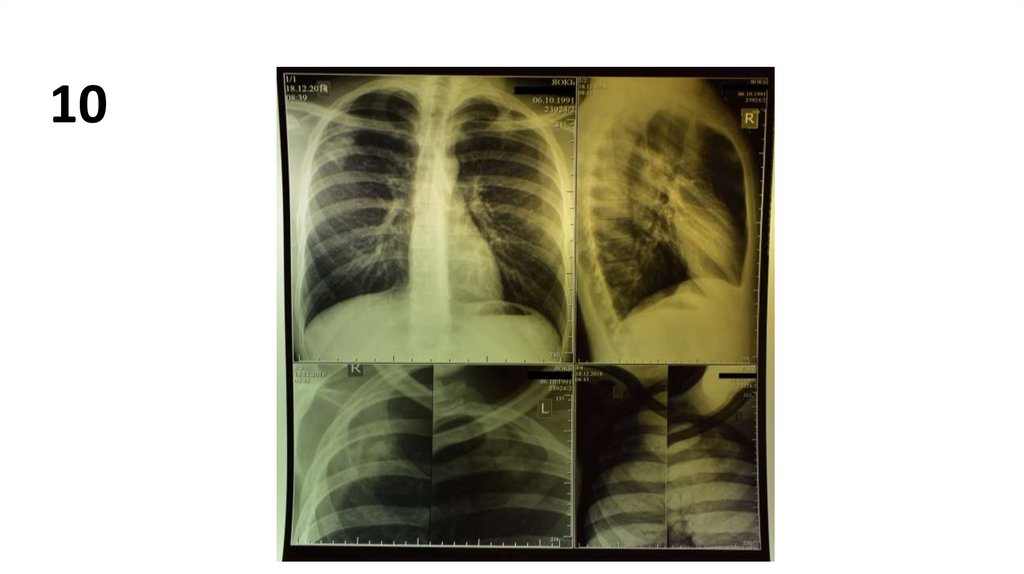

10.

10